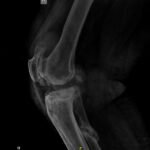

It is a complex joint made of three bones (Patella, Femur and Tibia). It is more complicated than a simple hinge joint. There are three compartments in the knee the knee.

In advanced stages of arthritis patient experiences pain on movement, disturbed sleep, stiffness, swelling and deformity. Sometimes pt needs walking stick and not relieved by non surgical treatment than total knee replacement is the operation of choice.

In this the arthritic and eroded joint surface is removed and replaced with an artificial knee prosthesis made of specialized metal and high grade plastic. The operation also corrects the deformity if present.